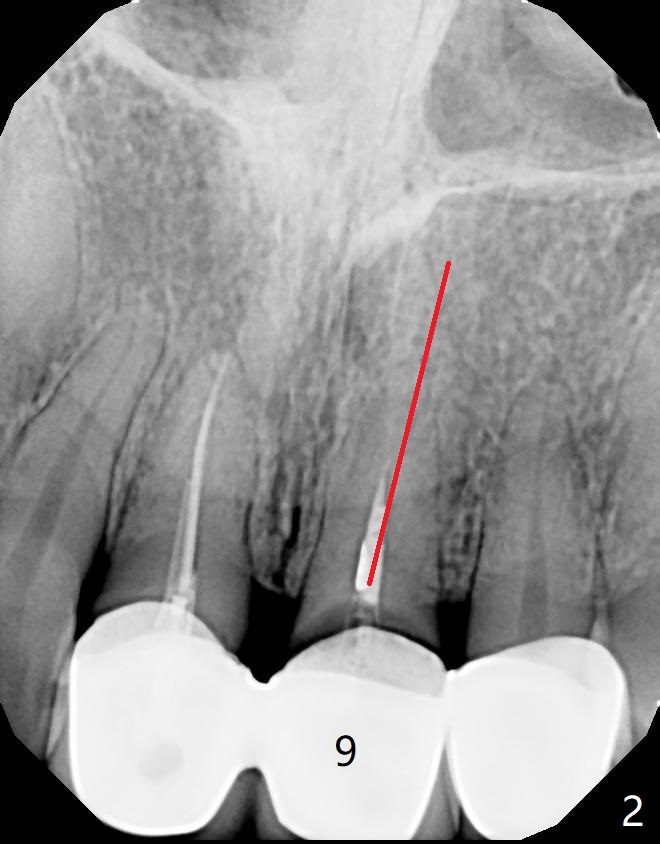

Loose FPD A 29-year-old woman has multiple restoration (Fig.1). Recently the upper anterior bridge is loose. It appears that there is breakage between #9 and 10 and that the tooth #9 is non-salvageable (Fig.2). The FPD will be sectioned between #8 and 9. It is possible that the tooth #8 is non-salvageable. Since the bone height is not ample, an implant system with high stability will be chosen for this case. Osteotomy will be established slightly distal to avoid the Incisive Canal. Photos will be taken preop. Do not forget the Planning Kit; angled abutment may be used. Return to

Upper

Incisor Immediate Implant,

Armaments,

Metronidazole Xin Wei, DDS, PhD, MS 1st edition 02/07/2018, last revision 08/12/2018 |